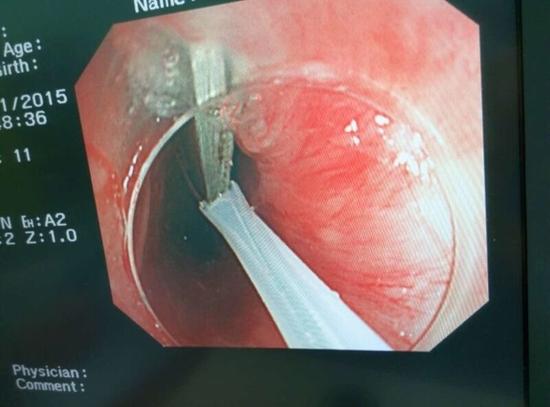

醫(yī)生從華先生胃里取出的鑷子和打火機(jī)

手術(shù)中,范醫(yī)生通過胃鏡準(zhǔn)確發(fā)現(xiàn)了胃里的鑷子。但讓他驚訝的是,在華先生胃底竟然還躺著三個(gè)被腐蝕了的打火機(jī),打火機(jī)的金屬部件都已經(jīng)不見了。

隨后,范醫(yī)生先用圈套器套取出了長10厘米的鑷子,再一個(gè)一個(gè)地取出了打火機(jī)。整個(gè)取出過程小心謹(jǐn)慎而又一氣呵成,只用了不到10分鐘。